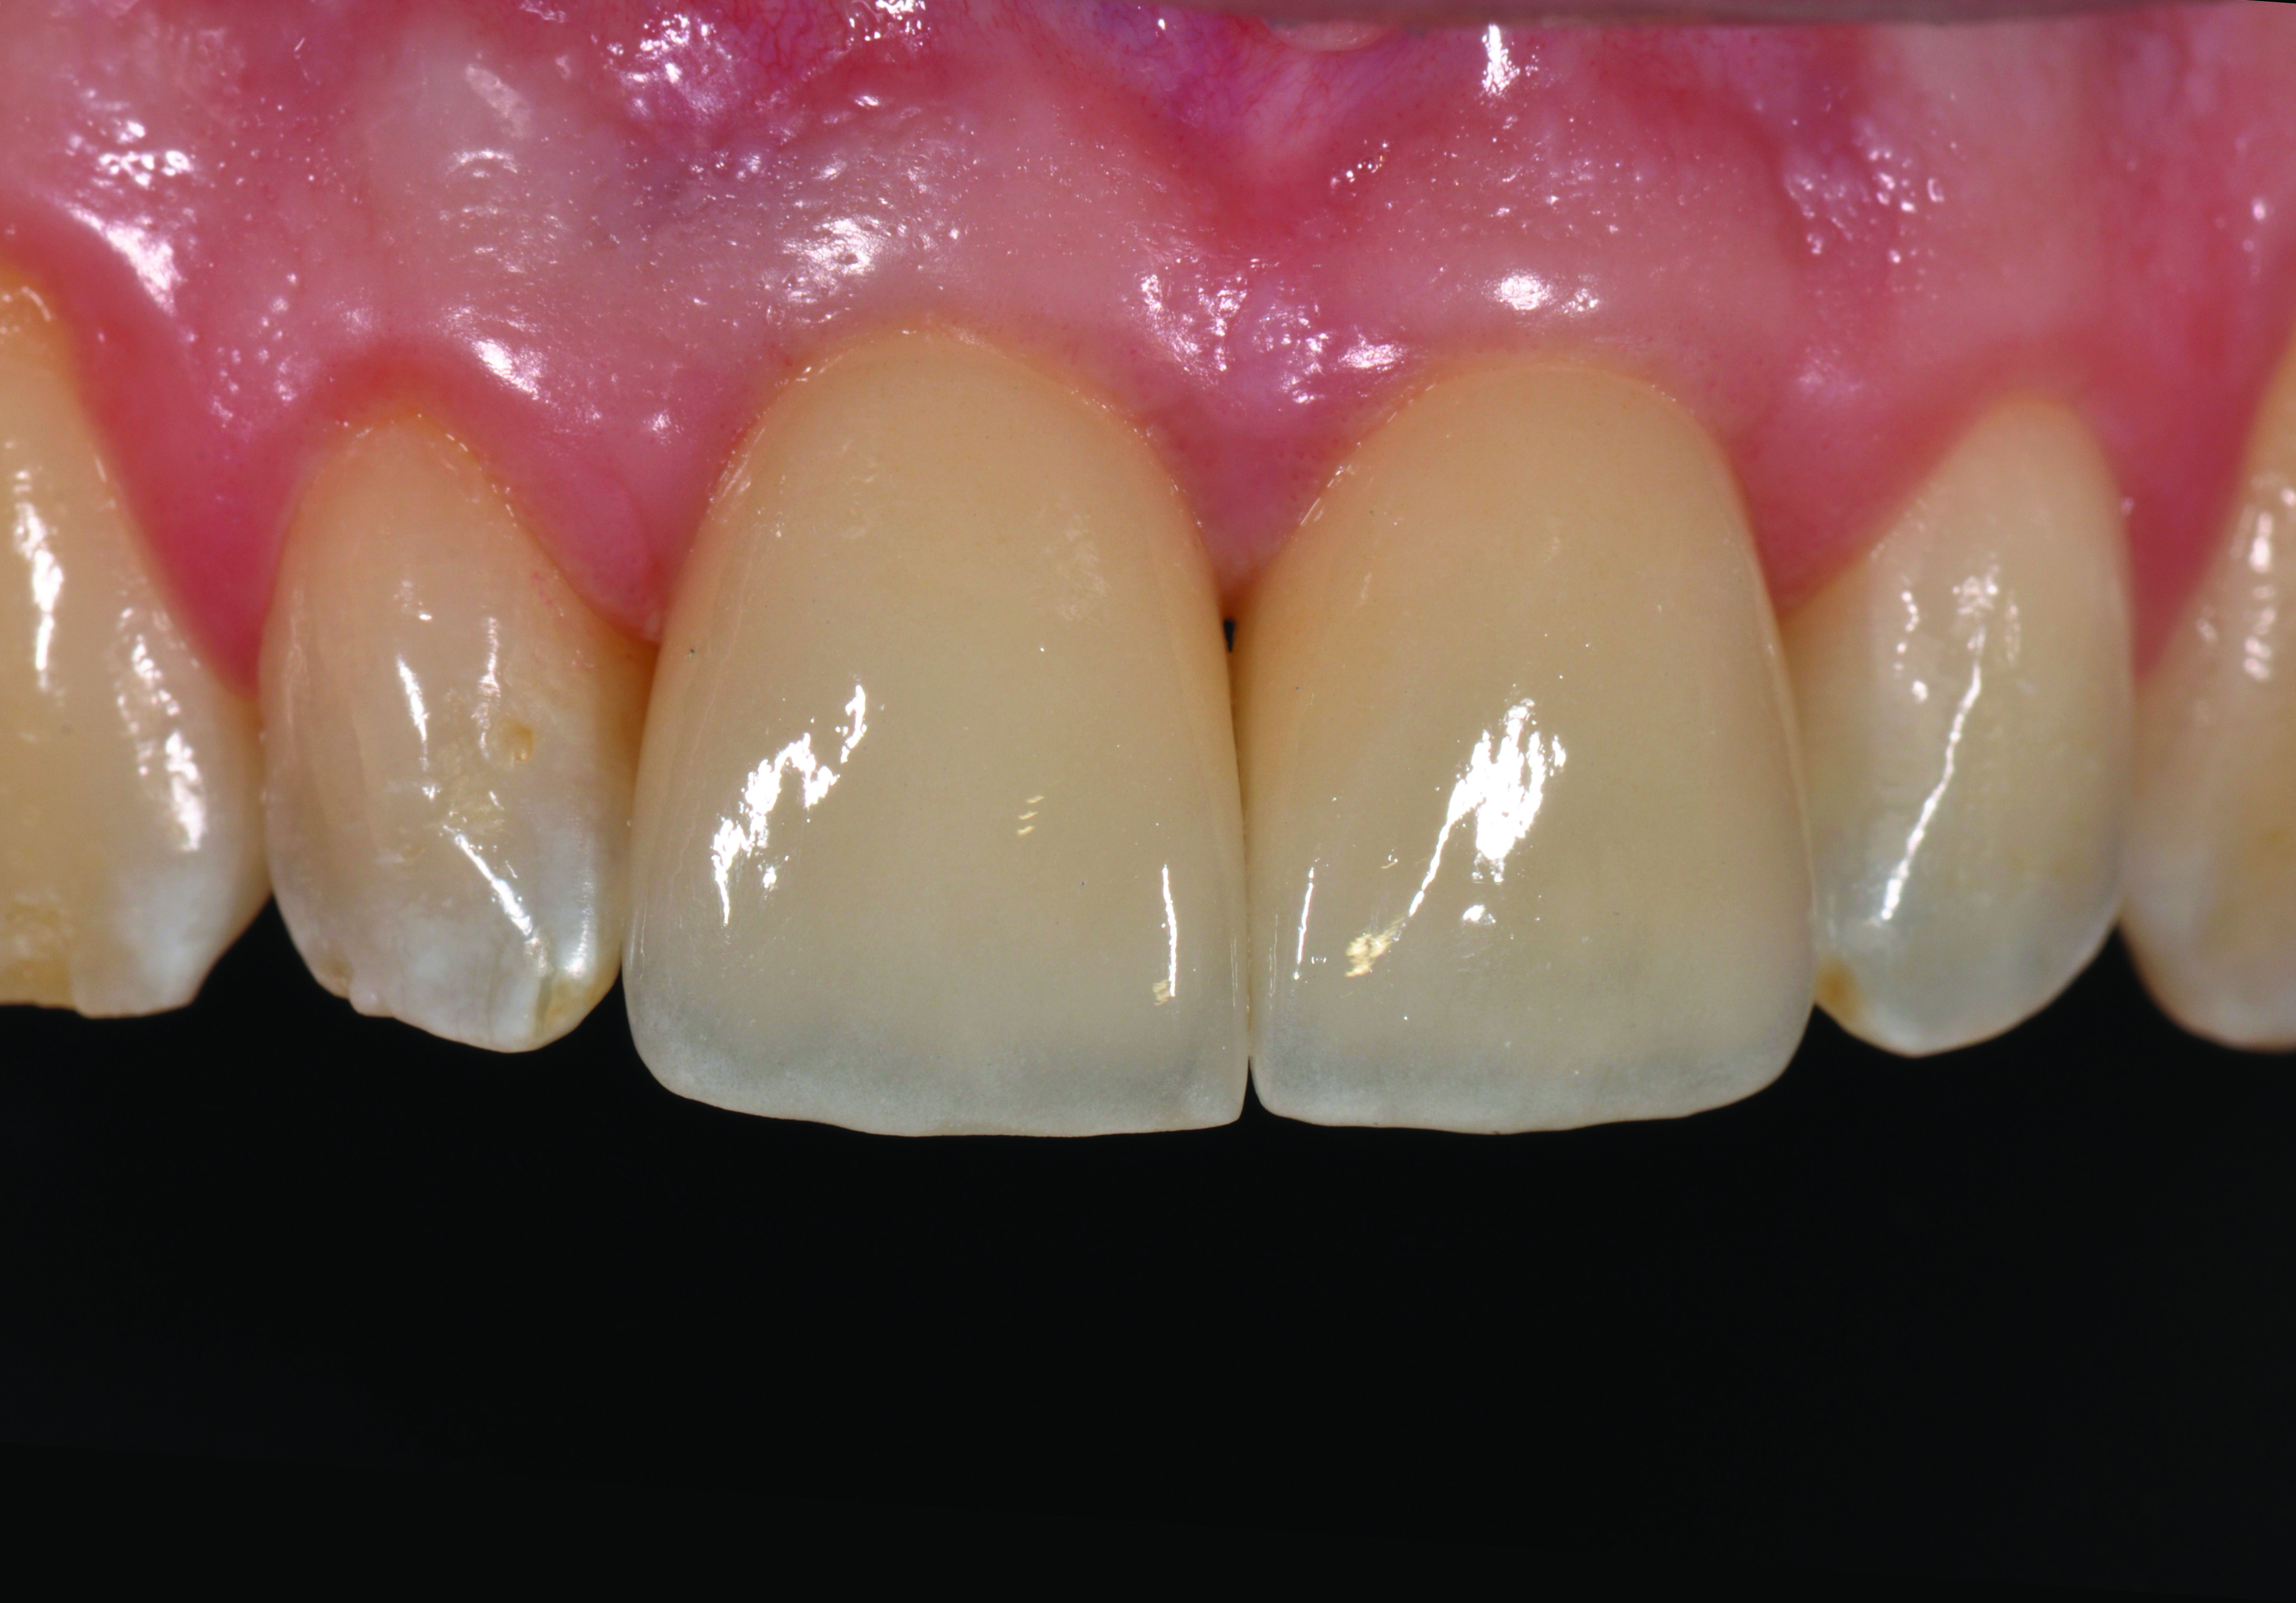

Fig 19. Prepared tooth No. 8 and customization of a stock impression coping for final impression.

Figure 19

Fig 20. Delivery of an ideally contoured zirconia abutment with a cement line that is minimally submerged and which mimics the preparation of the adjacent incisor.

Figure 20

After a 3-month integration period, removal of the provisional restoration shows well-developed tissue surrounding the implant collar (Figure 18). The adjacent tooth was prepared and impressed for a porcelain restoration, and an impression coping was customized to record the position of the implant and its soft-tissue anatomy (Figure 19). Zirconia is increasingly recognized as an abutment material with many benefits in the esthetic zone, but its success is clearly linked to basic decisions in the surgical phase of treatment. An ideally designed zirconia abutment mimics the preparation of the adjacent No. 8, with minimal submergence of the margin on the implant and natural tooth (Figure 20); the ideal restorative result demands a pleasing balance of white and pink.